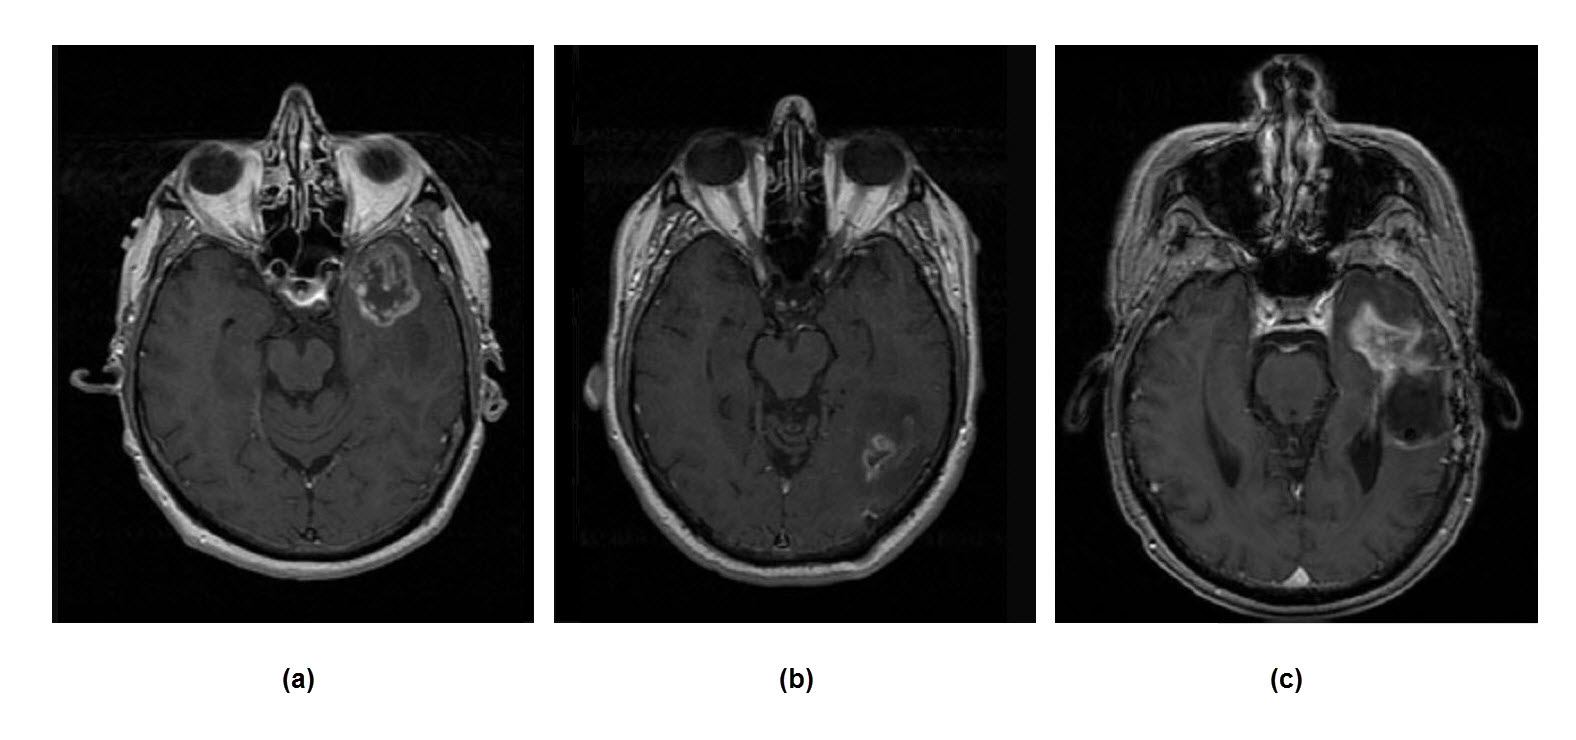

Fig.2 shows a sample sequence of dataset for one patient for 5 consecutive slices (Axial T1 GD enhanced MRI). Also, a sample image for each tumor grade for the same dataset is shown in Fig.3. It is obvious from Fig.2 and Fig.3, that while there isn’t significant interclass variation among the tumors, there exist notable intraclass difference among them; which makes the detection of tumors a challenging task even for experts.